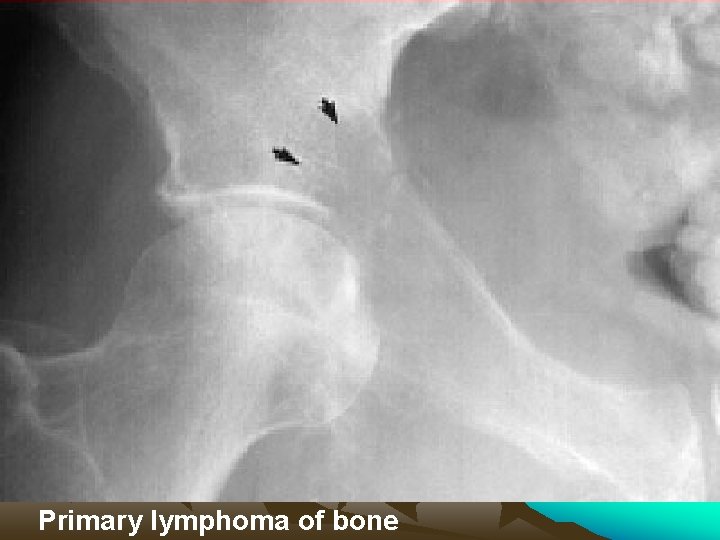

Primary lymphoma of bone

Primary lymphoma of bone